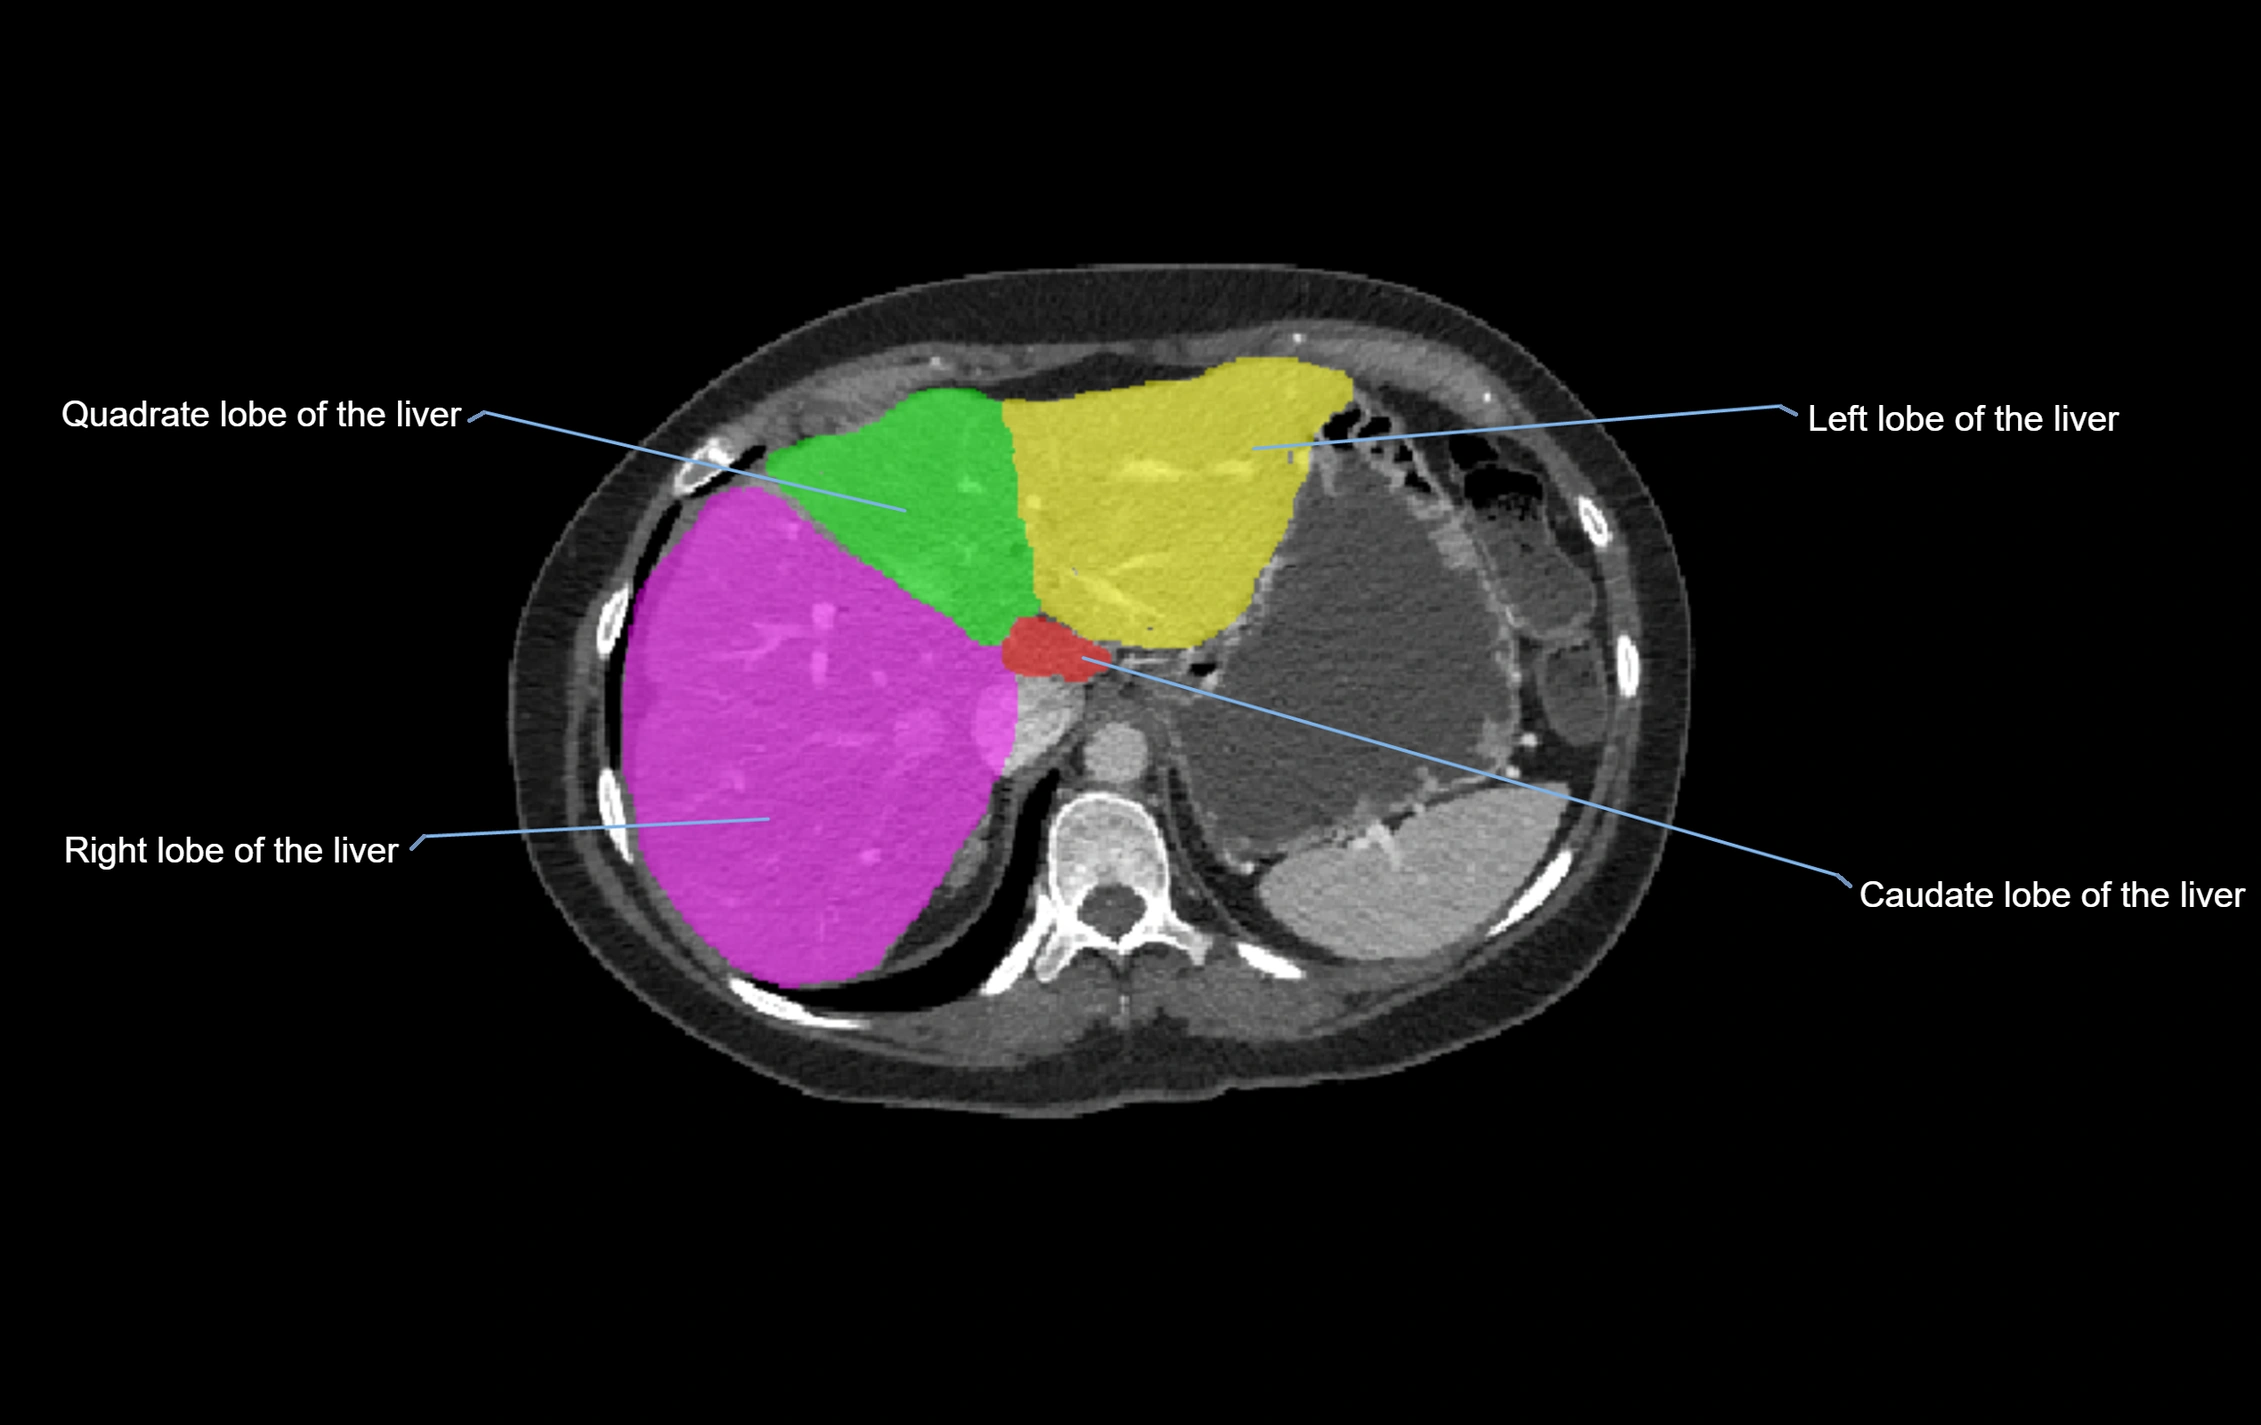

CT Appearance

CT Pre-Contrast:

• Caudate lobe appears as a soft-tissue density, isodense to the rest of the liver

• Enlargement may be appreciated in cirrhosis or Budd–Chiari syndrome

CT Post-Contrast:

• Homogeneous enhancement in the portal venous phase, similar to rest of liver

• Independent venous drainage into the IVC may be visualized

• Lesions follow characteristic CT enhancement patterns (HCC: arterial hyperenhancement with washout; hemangiomas: peripheral nodular enhancement with centripetal fill-in)

CT Venous Phase (functional significance):

• Caudate lobe often enhances relatively more than other lobes in Budd–Chiari syndrome, due to preserved venous outflow

CT Image

image